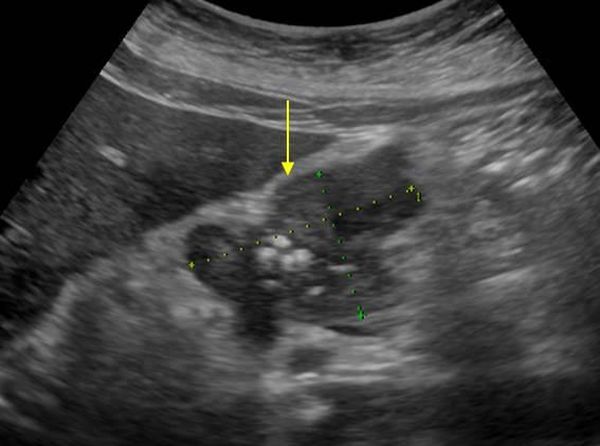

Рак на УЗИ выглядит в виде объёмного образования в структуре органа. Оно может выявиться в зоне головки, тела или хвоста. На УЗИ визуализируется размер, форма и плотность опухоли. При раке головки отмечают её увеличение. Она приобретает округлую форму. Выявляют распространение злокачественного процесса на соседние органы, прорастание опухоли в близлежащие сосуды, появление метастатических очагов в лимфатических узлах.

Опухоли поджелудочной железы на УЗИ

Опухоль на мониторе аппарата УЗИ просматривается в качестве объемного новообразования, имеющая неправильную форму и неровные края. Наблюдается изменение тканей поджелудочной железы низкой эхогенности. Образование неоднородной структуры. Нередко возникают сложности дифференциации образования от псевдотуморозной формы панкреатита, потому требуется тщательное исследование панкреатического канала. При болезни основной панкреатический проток выглядит расширенным, на своем протяжении его диаметр неравномерный. Когда есть рак, канал расширяется только ниже опухоли.

При проведении УЗИ можно увидеть характерный эхопризнак ракового новообразования — значительное увеличение отдельной части железы или выбухание ее контура. В 50-80% случаев в онкозаболевание вовлекается головка ПЖ. Даже опухоль незначительных размеров является хорошо видимой в головном конце на УЗИ. Это связано со следующими причинами:

Онкологический процесс в виде опухоли маленьких размеров в хвостовой части выявляется на УЗИ намного реже. О наличии новообразования такой локализации свидетельствуют признаки, подробно описываемые в расшифровке УЗИ (его протоколе). Исследование может показывать:

При раке ПЖ изменяются контуры органа: они становятся нечеткими, но, в отличие от хронического панкреатита, не имеют неровностей или зазубрин. В месте расположения опухоли визуализируются выпуклости, которые проникают в окружающую клетчатку в виде языков. Все это подробно описывается в заключении УЗИ.

В основном раковое образование ПЖ является гипоэхогенным, в нем не содержится внутренних эхоструктур. Но бывают опухоли с диффузно определяющимися эхосигналами или высокоинтенсивными эхосигналами в центре узла при отсутствии их на периферии опухоли. Граница между измененной опухолью и остальной тканью железы может быть нечеткой, но приблизительно видна всегда за счет разности в эхогенности нормальной и патологической ткани. Несмотря на схожесть структуры ткани образования (особенно если в ней отсутствуют участки структур с повышенной плотностью) с кистой, УЗИ с помощью эффекта дистального усиления дает возможность отдифференцировать злокачественный очаг от жидкостного образования.